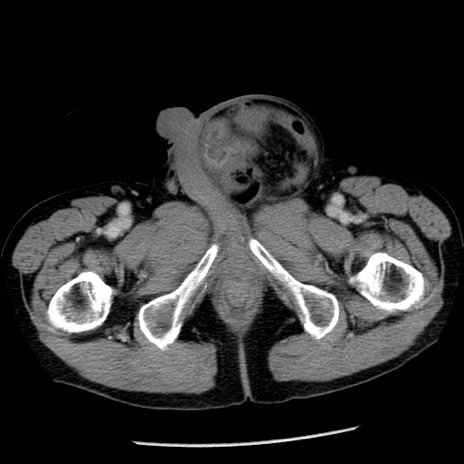

症例26(横断像)

【症例】80歳代男性

【主訴】嘔吐

【現病歴】昨晩2回嘔吐あり、今朝になっても嘔吐あり。来院。

【既往歴】胃潰瘍

【身体所見】意識清明、BT 37.6℃、BP 166/95mmHg、HR 100bpm、SpO2 97%、腹部:平坦・軟、腸蠕動音聴取良好、圧痛なし。

【データ】WBC 21900、CRP 1.46